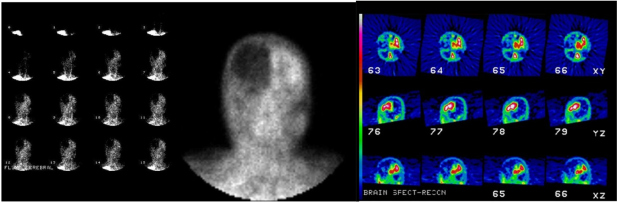

SPECT de Perfusão Cerebral com radiofármacos específicos

- Imagens planas tardias ou SPECT. Sempre antes de analisar as imagens de SPECT, deve-se olhar a aquisição em cine para confirmar que todas as projeções foram adquiridas, que não houve movimentação significativa, checar a relação alvo-atividade de fundo. Deve-se dar preferência para a escala de cinza ao invés das coloridas, devido a maior sensibilidade da escala de cinza em baixa atividade.

- No exame positivo para morte encefálica, ocorre ausência completa de captação cerebral do radiofármaco. Deve-se verificar se não há captação em todo o cérebro incluindo os hemisférios cerebrais bilateralmente, os hemisférios cerebelares e o tronco cerebral. Se forem adquiridas apenas imagens planas deve-se realizar no mínimo as projeções anterior e posterior e pelo menos uma projeção lateral para a análise da fossa posterior.

- O sinal do hot nose também pode estar presente neste estudo nas imagens de fluxo sanguíneo, imagens estáticas e imagens tomográficas SPECT (fig. 1).

- Ausência completa de fluxo sanguíneo cerebral e cerebelar (fig. 2).

- Fluxo sanguíneo cerebral presente, apesar de anormal; nesse caso, descrever áreas de presença e ausência do fluxo (fig. 3).

- Fluxo sanguíneo cerebral normal (fig. 4).